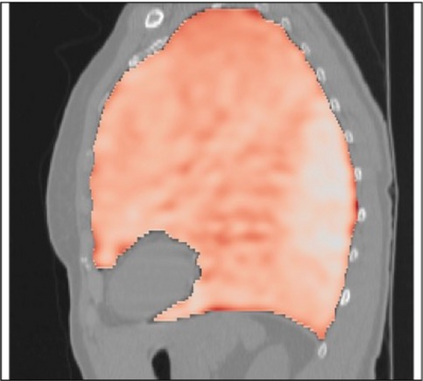

Deformable image registration is a fundamental task in medical image analysis and plays a crucial role in a wide range of clinical applications. Recently, deep learning-based approaches have been widely studied for deformable medical image registration and achieved promising results. However, existing deep learning image registration techniques do not theoretically guarantee topology-preserving transformations. This is a key property to preserve anatomical structures and achieve plausible transformations that can be used in real clinical settings. We propose a novel framework for deformable image registration. Firstly, we introduce a novel regulariser based on conformal-invariant properties in a nonlinear elasticity setting. Our regulariser enforces the deformation field to be smooth, invertible and orientation-preserving. More importantly, we strictly guarantee topology preservation yielding to a clinical meaningful registration. Secondly, we boost the performance of our regulariser through coordinate MLPs, where one can view the to-be-registered images as continuously differentiable entities. We demonstrate, through numerical and visual experiments, that our framework is able to outperform current techniques for image registration.